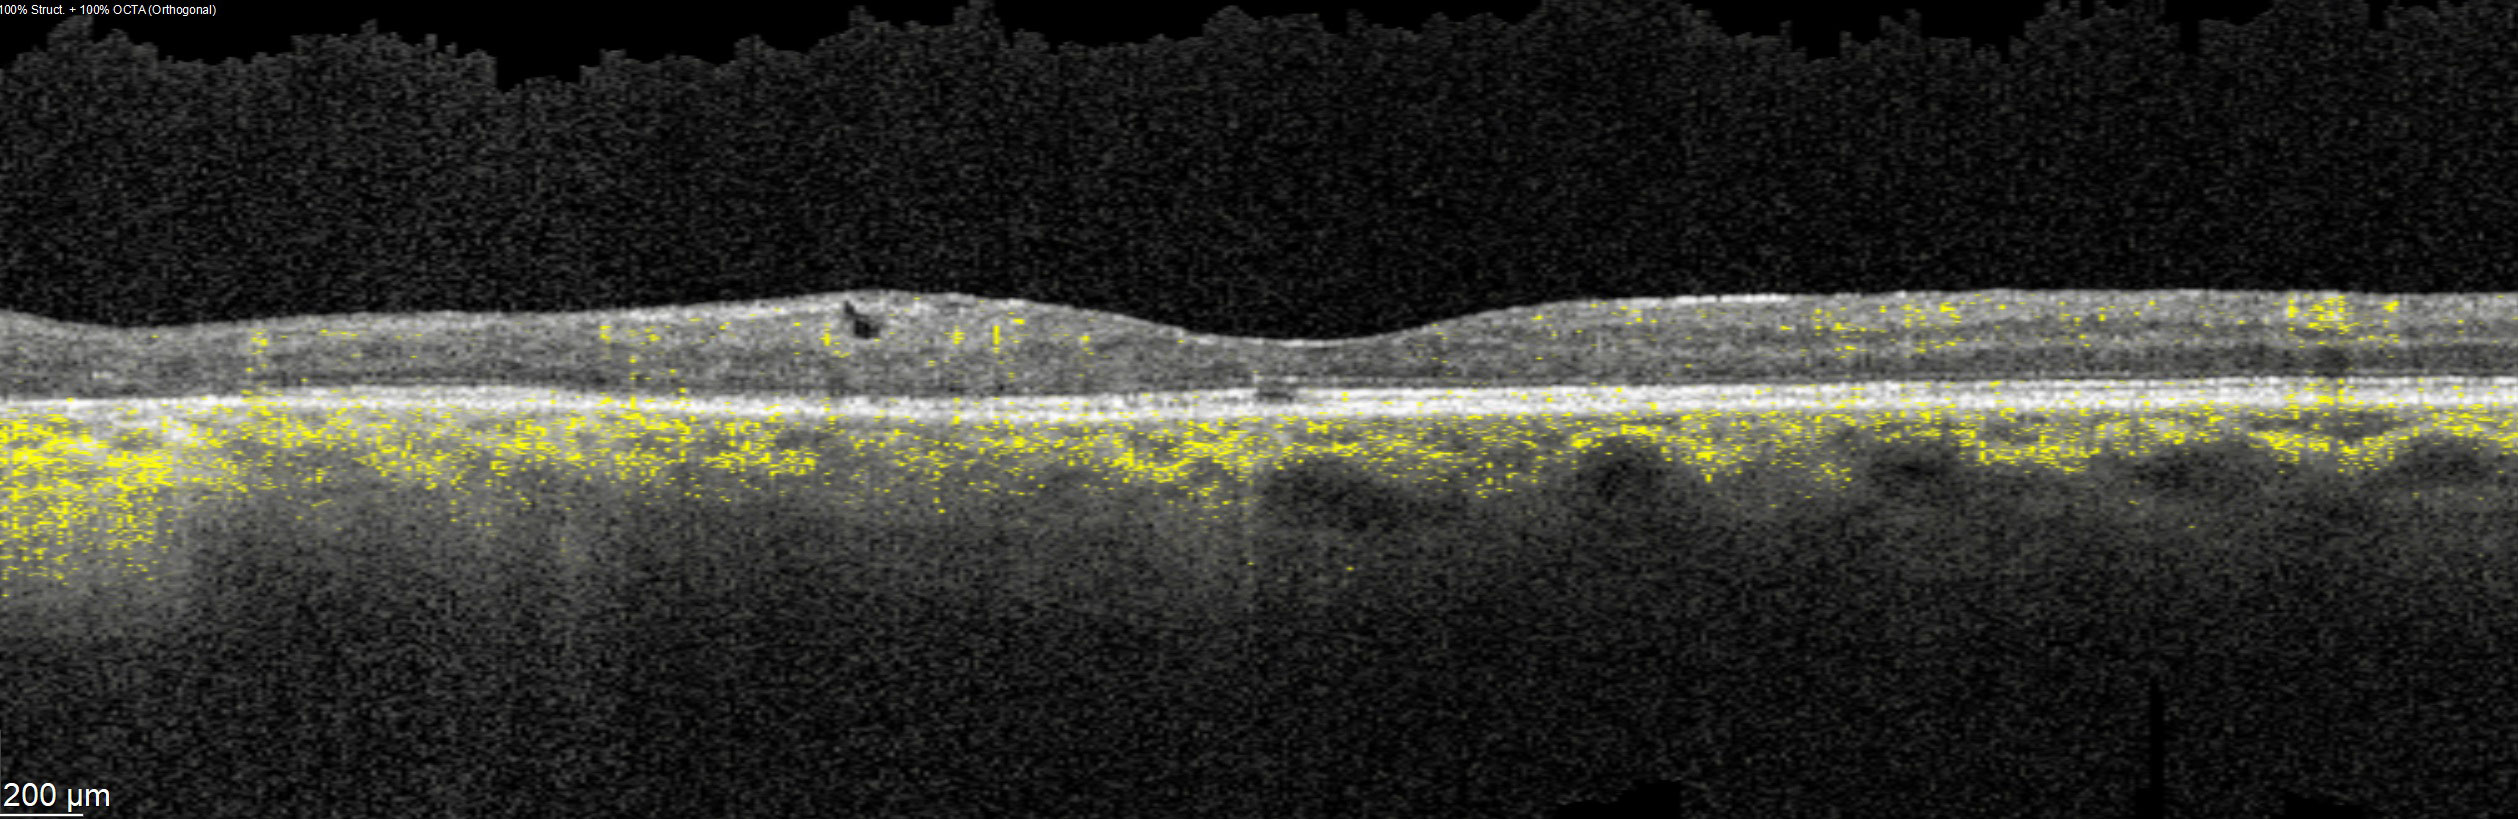

Offering the ideal speed-quality ratio for OCTA, 125 kHz allows you to increase your throughput without any clinically relevant loss in image quality in comparison to the current 85 kHz scan speed. The fast acquisition of images allows for visualization of flow, even in miniscule vessels, while minimizing artefacts, resulting in sharp and detailed images of the capillary network. Additionally, you can decrease chair time when you speed up acquisition with the Glaucoma Module Premium Edition in your glaucoma workflow, if applicable.

SPECTRALIS with SHIFT technology and 125 kHz scan speed empowers you to offer customized diagnostic OCTA imaging of both the retina and the optic nerve head to meet the needs of each individual patient – or adjust to 85 kHz if your patient’s condition requires longer light exposure.

125 kHz – A fast scan speed for improved workflow and high OCTA image quality.